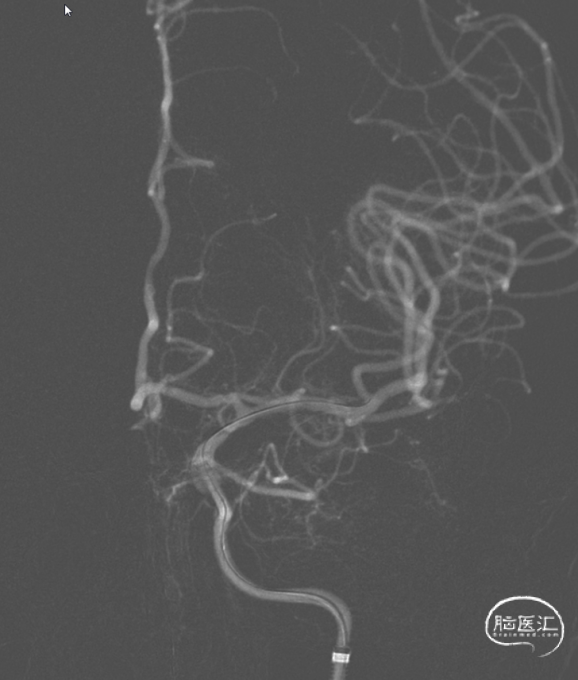

造影确认,闭塞段血流恢复,提示微导管首过效应阳性,残留颈内动脉交通段重度狭窄,串珠样改变,考虑原位狭窄,予替罗非班针微泵维持。

球囊扩张1次,狭窄较前改善,停留10分钟观察,狭窄段血管未见明显回缩,最终造影提示闭塞段血流恢复,mTICI 3级。

残余狭窄,考虑到手术风险,拟二期支架置入。